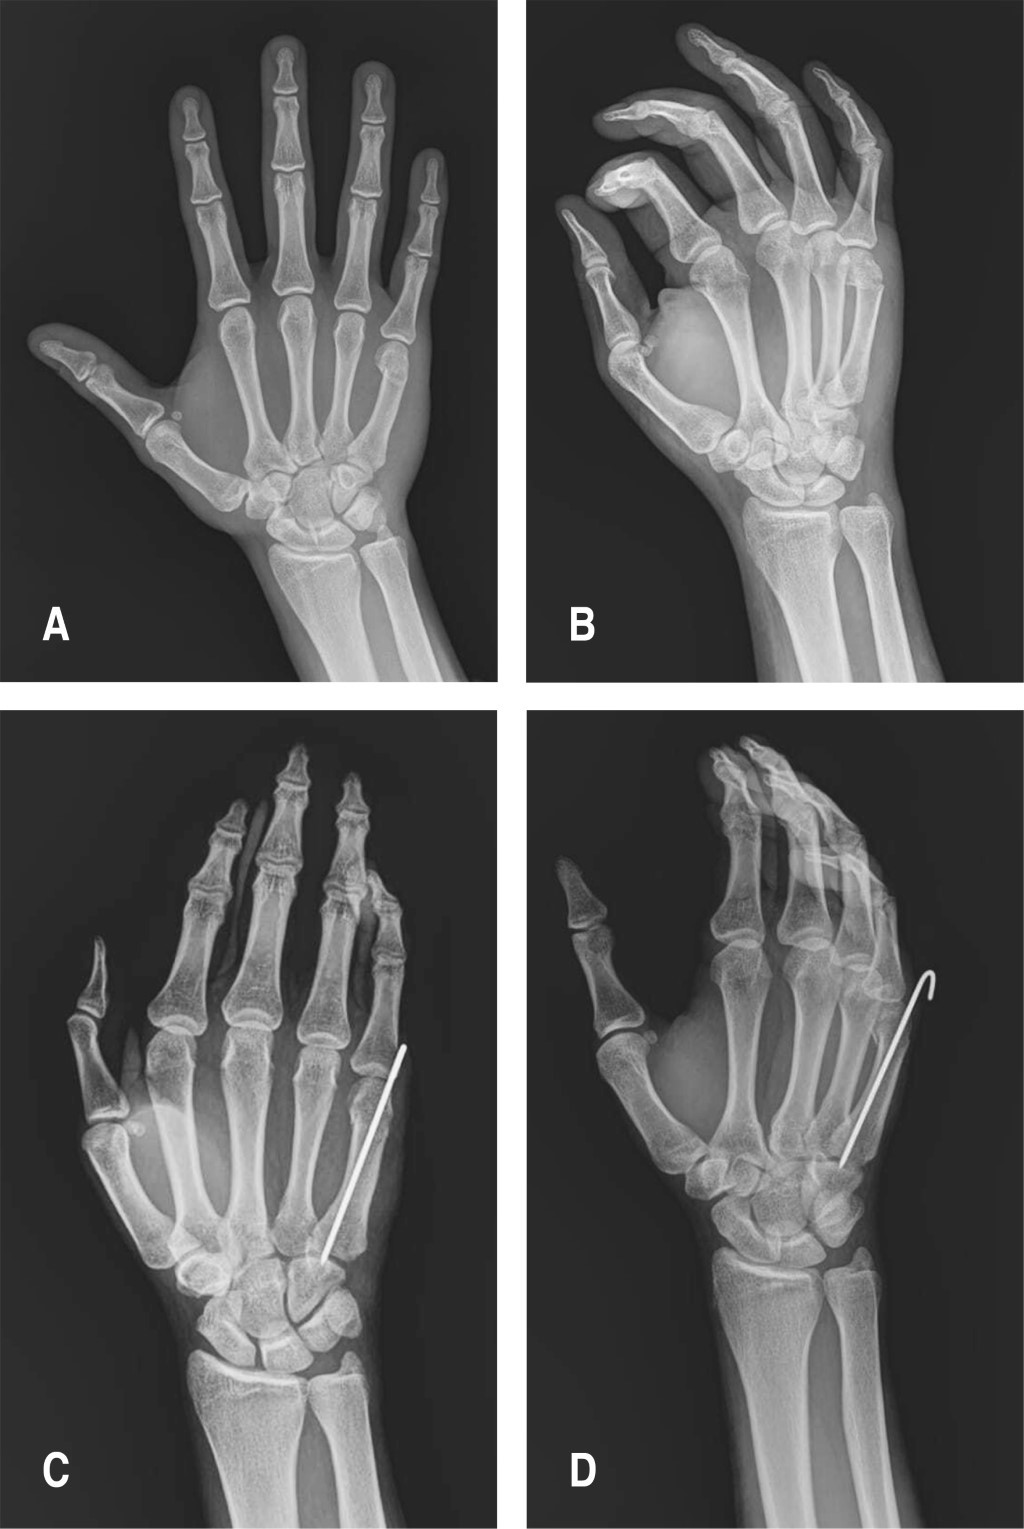

Figure 2